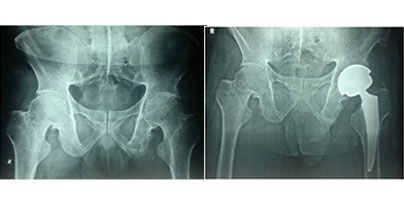

X-rays before and after total hip replacement. In this case, non-cemented components were used.